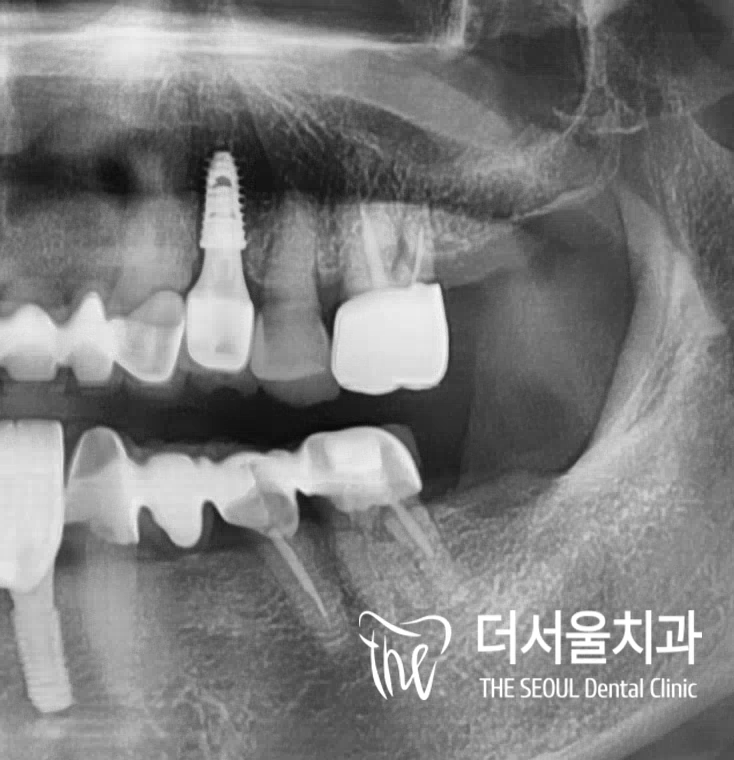

반갑습니다. 판교역 더서울 치과 쌍둥이 박현성 원장입니다. 오늘 보여드릴 임플란트 케이스는 조금 특이했다고 말씀드릴 수 있는데요. 환자분께서는 초등학교를